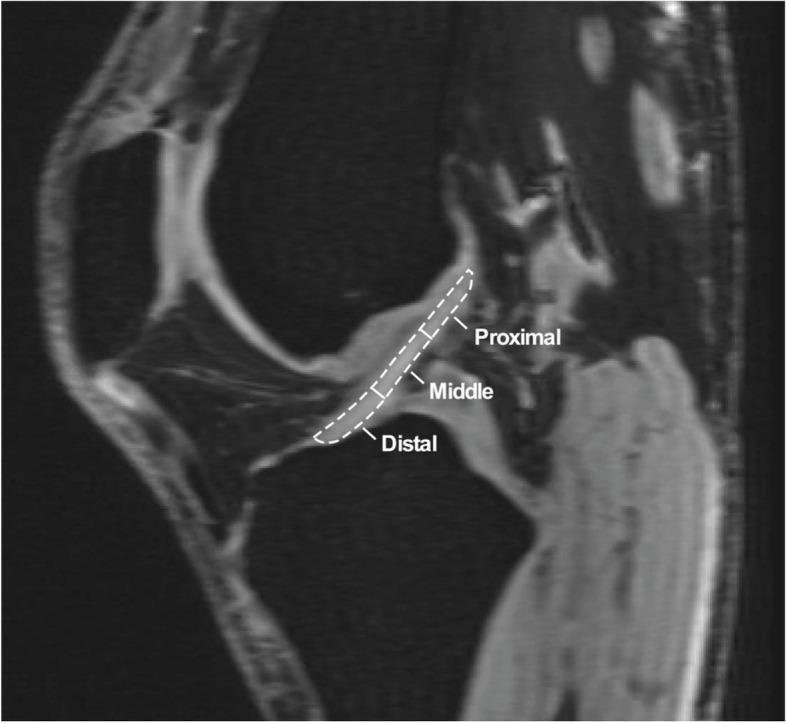

Fourteen cadaveric knees were studied (8 females, 6 males), age 25-61 years. Superficial femoral, anterior tibial, and posterior tibial arteries were cannulated; without intraarticular dissection. Contrast-enhanced quantitative-MRI was performed using a previously established protocol. ACL regions corresponding to proximal, middle, and distal thirds were identified on sagittal-oblique pre-contrast images. Signal enhancement (normalized to tibial plateau cartilage) was quantified to represent regional perfusion as a percentage of total ACL perfusion. Comparative statistics were computed using repeated measures ANOVA, and pairwise comparisons performed using the Bonferroni method.

Relative perfusion to proximal, middle, and distal ACL zones were 56.0% ±17.4%, 28.2% ±14.6%, and 15.8% ±16.3%, respectively (p = 0.002). Relative perfusion to the proximal third was significantly greater than middle (p = 0.007) and distal (p = 0.001). No statistically relevant difference in relative perfusion was found to middle and distal thirds (p = 0.281). Post-hoc subgroup analysis demonstrated greater proximal perfusion in males (66.9% ± 17.3%) than females (47.8% ± 13.0%), p = 0.036.

Using quantitative-MRI, in situ adult ACL demonstrated greatest relative perfusion to the proximal third, nearly 2 times greater than the middle third and 3 times greater than the distal third. Knowledge of differential ACL vascular supply is important for understanding pathogenesis of ACL injury and the process of biological healing following various forms of surgical treatment.